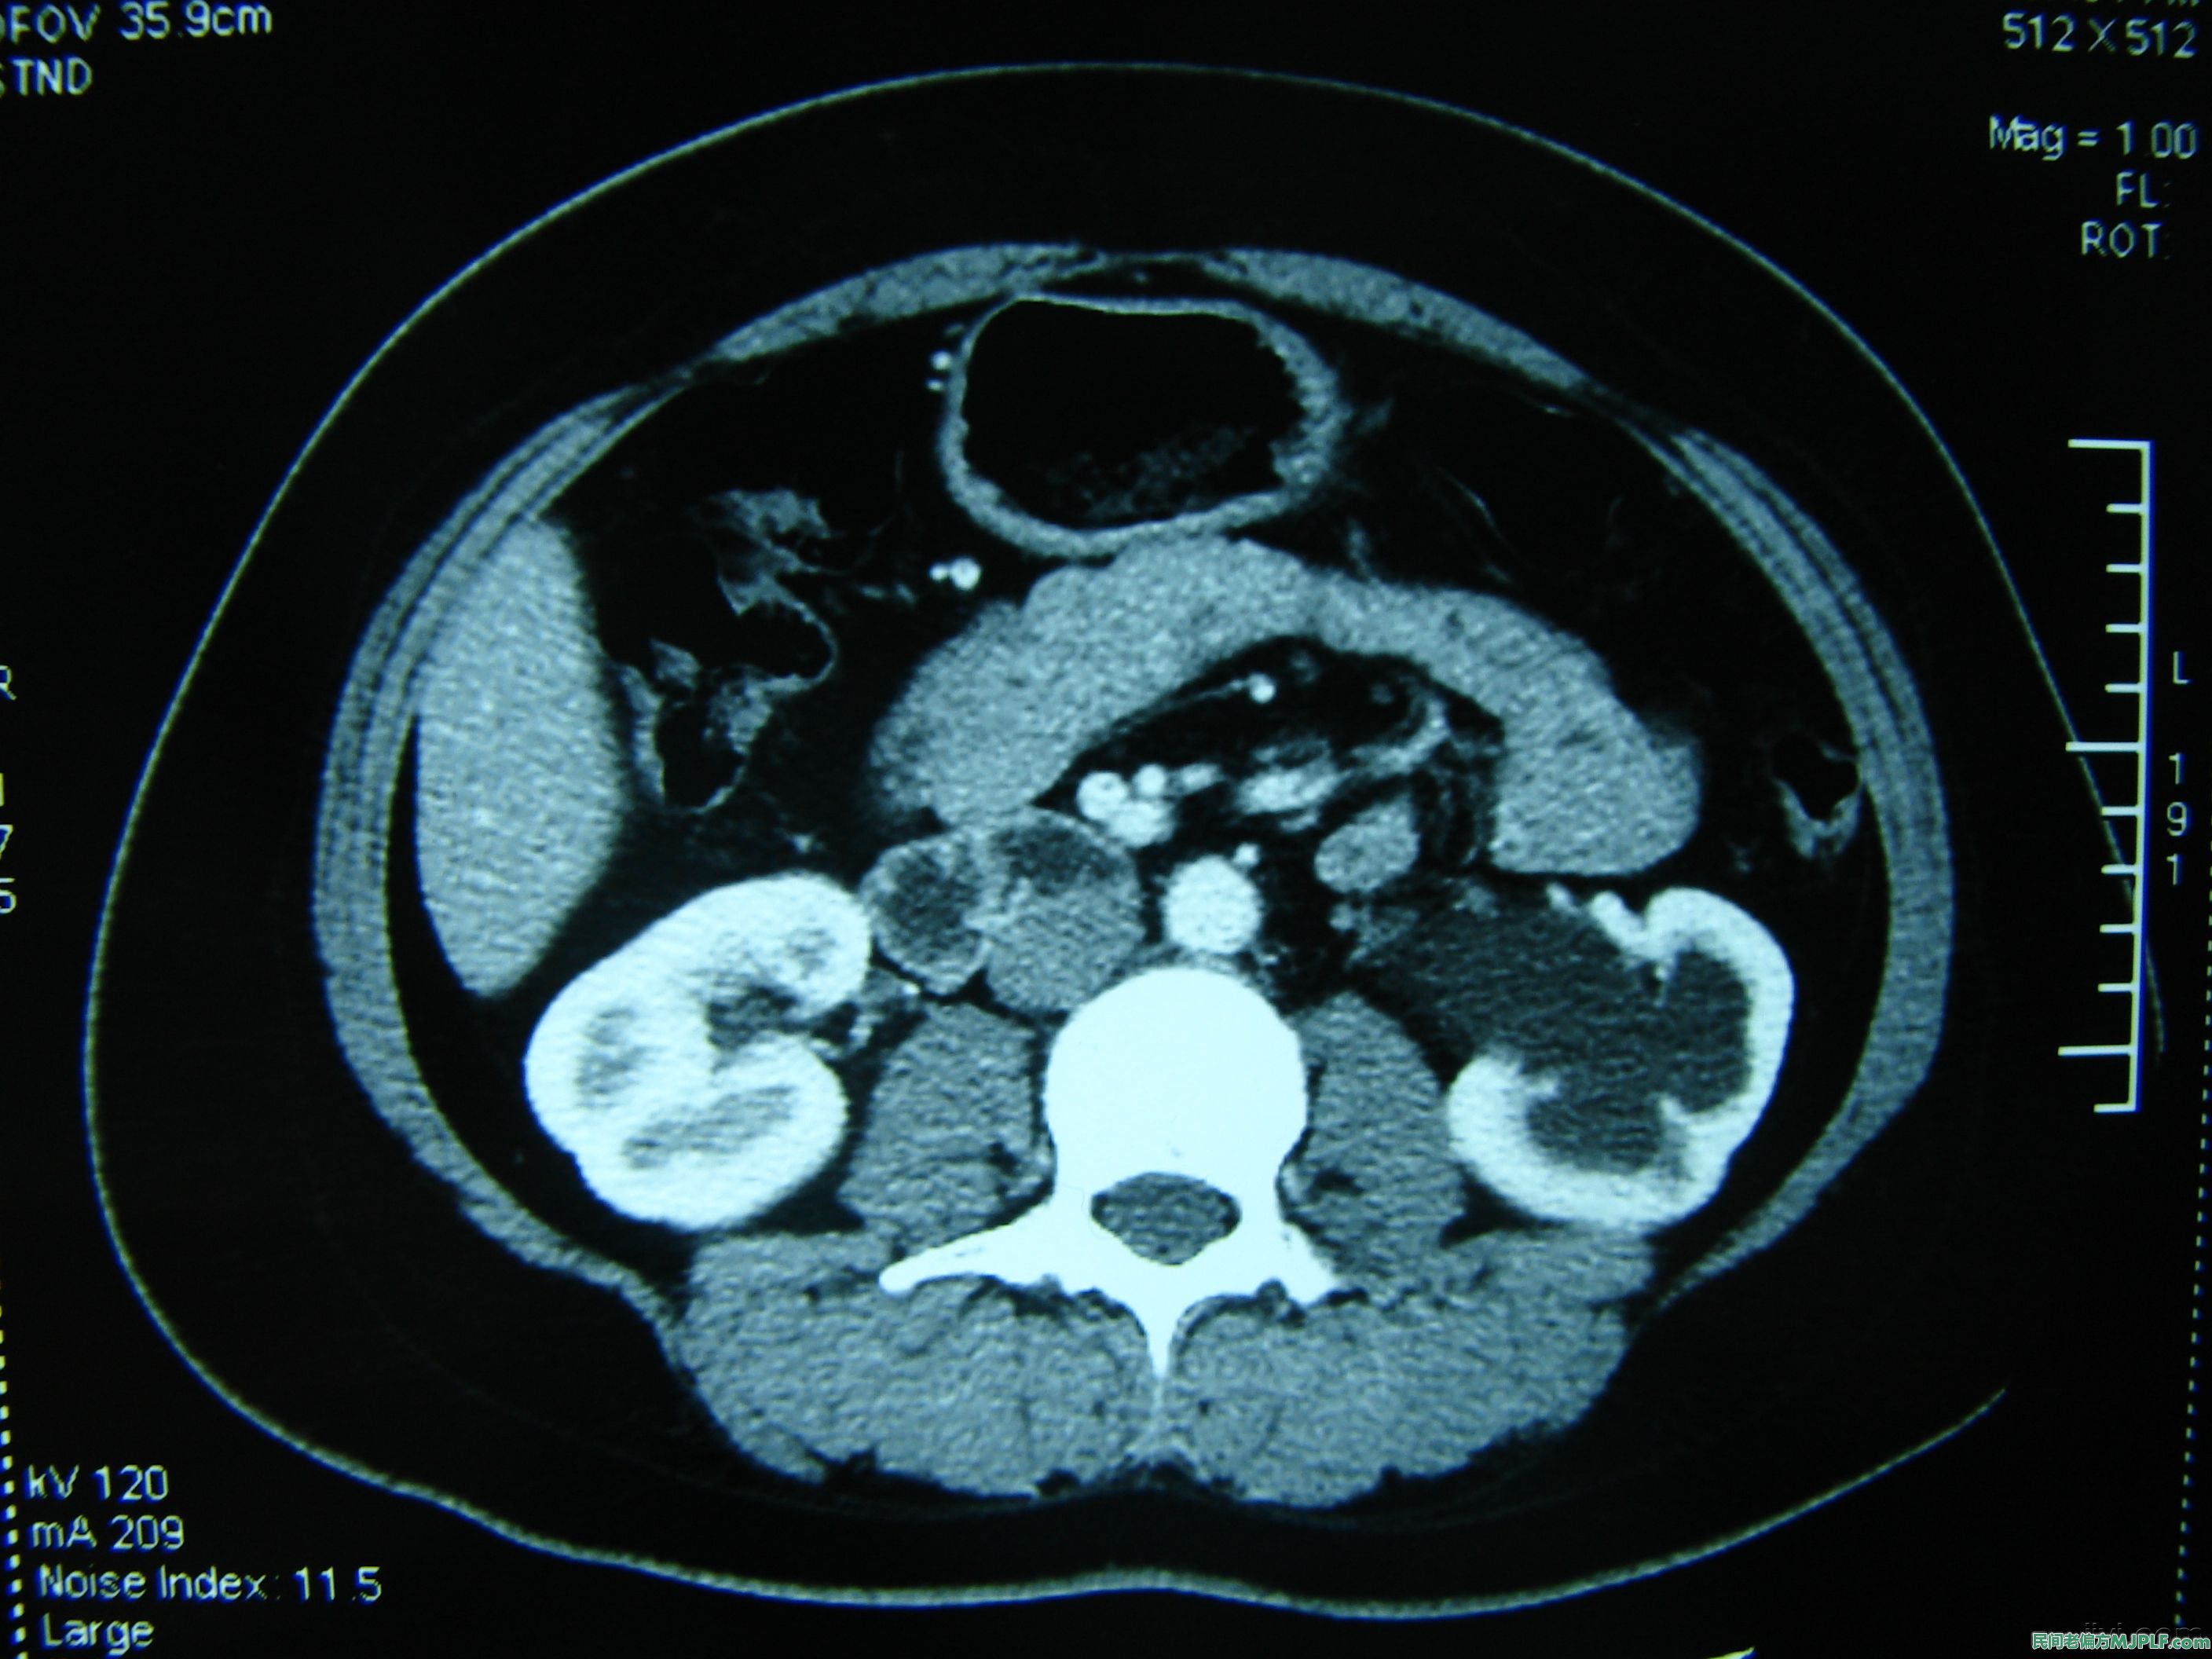

肾结石是由于各种原因导致的难溶性物质在肾盂肾盏等部位沉积,日久导致尿路梗阻,甚至影响肾功能的一种疾病。多发生在中壮年,男性多于女性。